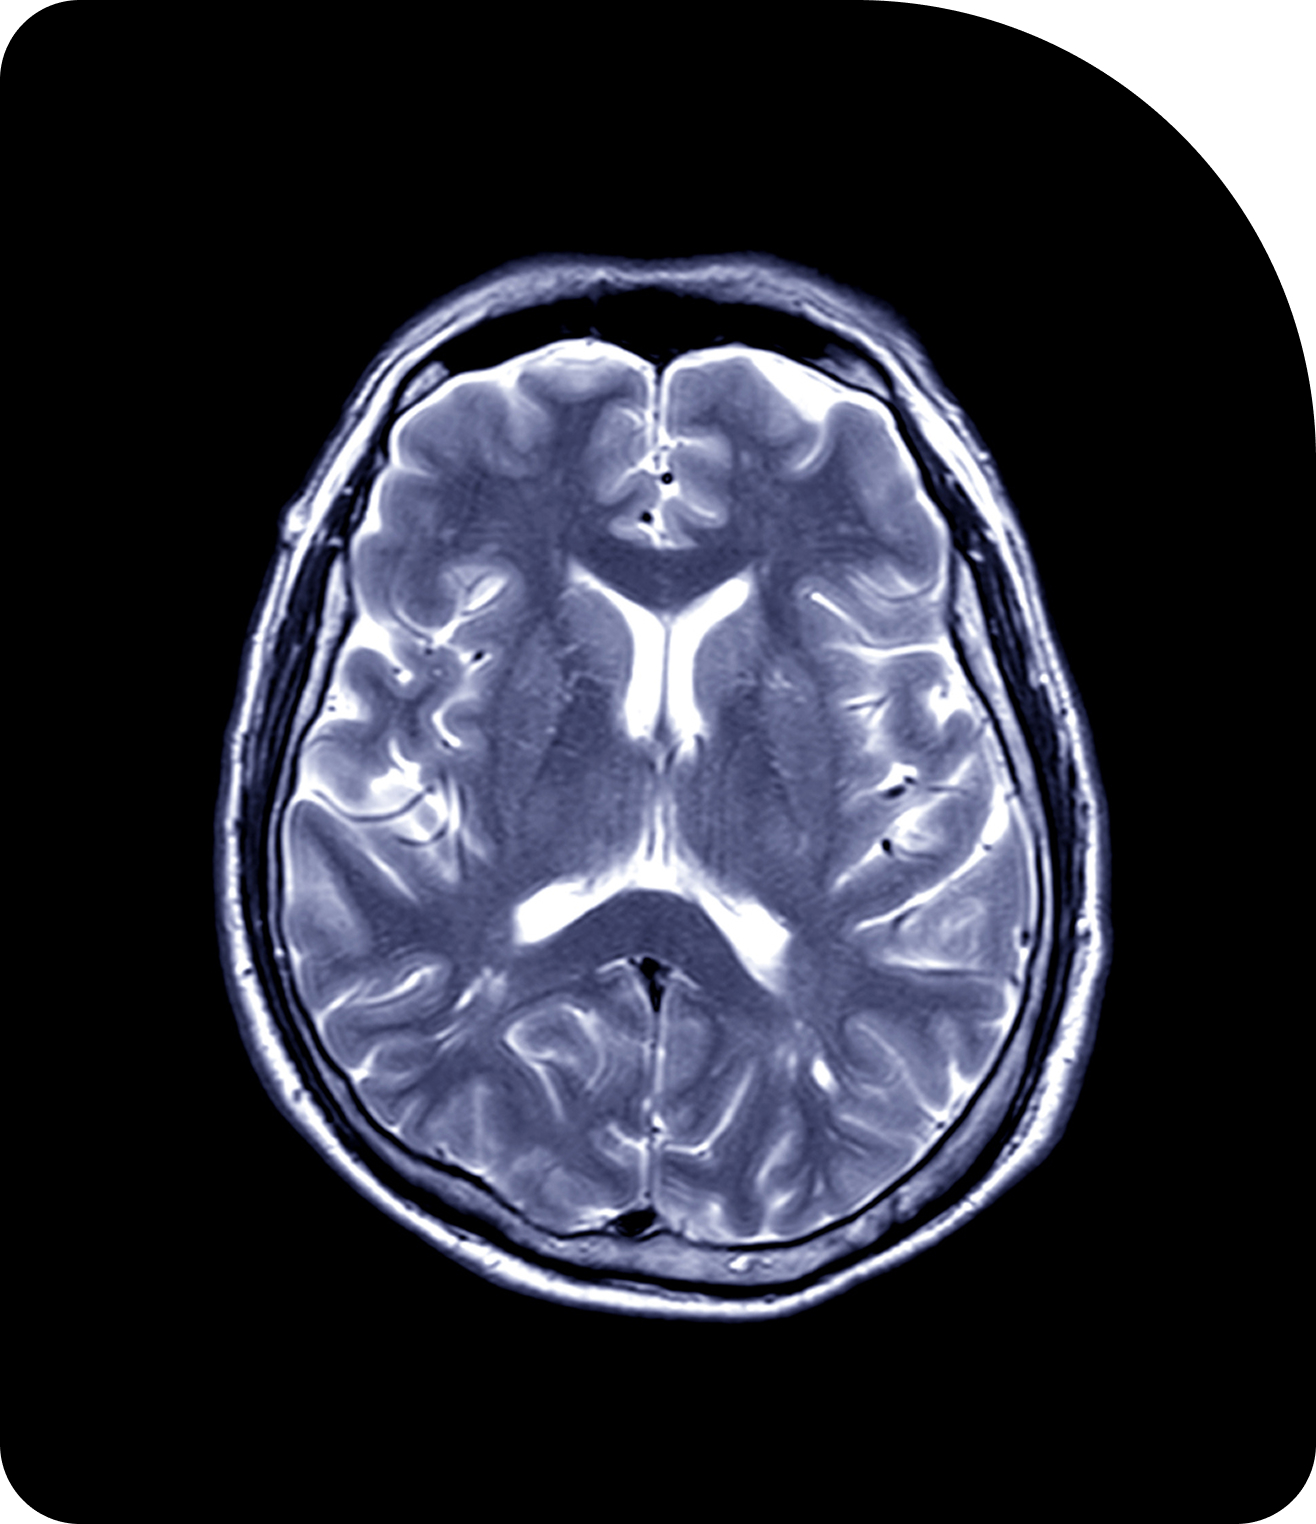

Compare Imaging TechnologiesAdaptive Radiotherapy in Action

| Brain (High-Grade Glioma) | UNITED (NCT04726397) & UNITED-3 (NCT05720078) | Sunnybrook Health Sciences Centre | Demonstrated feasibility of large margin reductions (40–71%) with MR-Linac Adaptive Radiotherapy. UNITED-3 expands to two-phase adaptive therapy for glioblastoma.[3] |